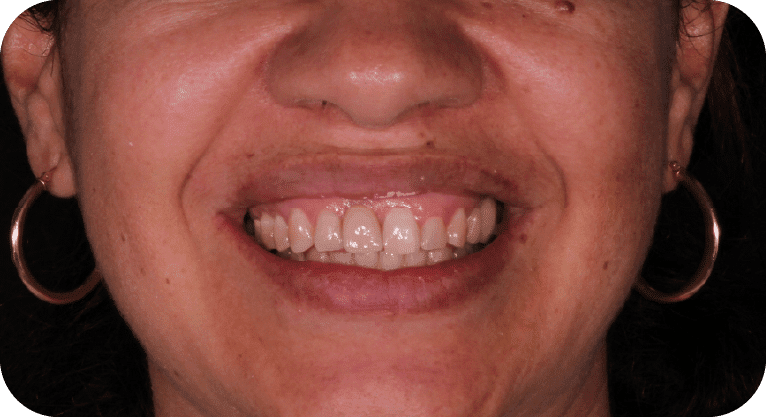

Paciente femenino, “29” años

Tratamiento: Carillas dentales

El paciente acudió a la clínica dental por inconformidad con la forma y posición de sus dientes. Tras una evaluación personalizada, se realizó un diseño de sonrisa con carillas dentales para mejorar su estética dental, logrando resultados naturales y satisfactorios.